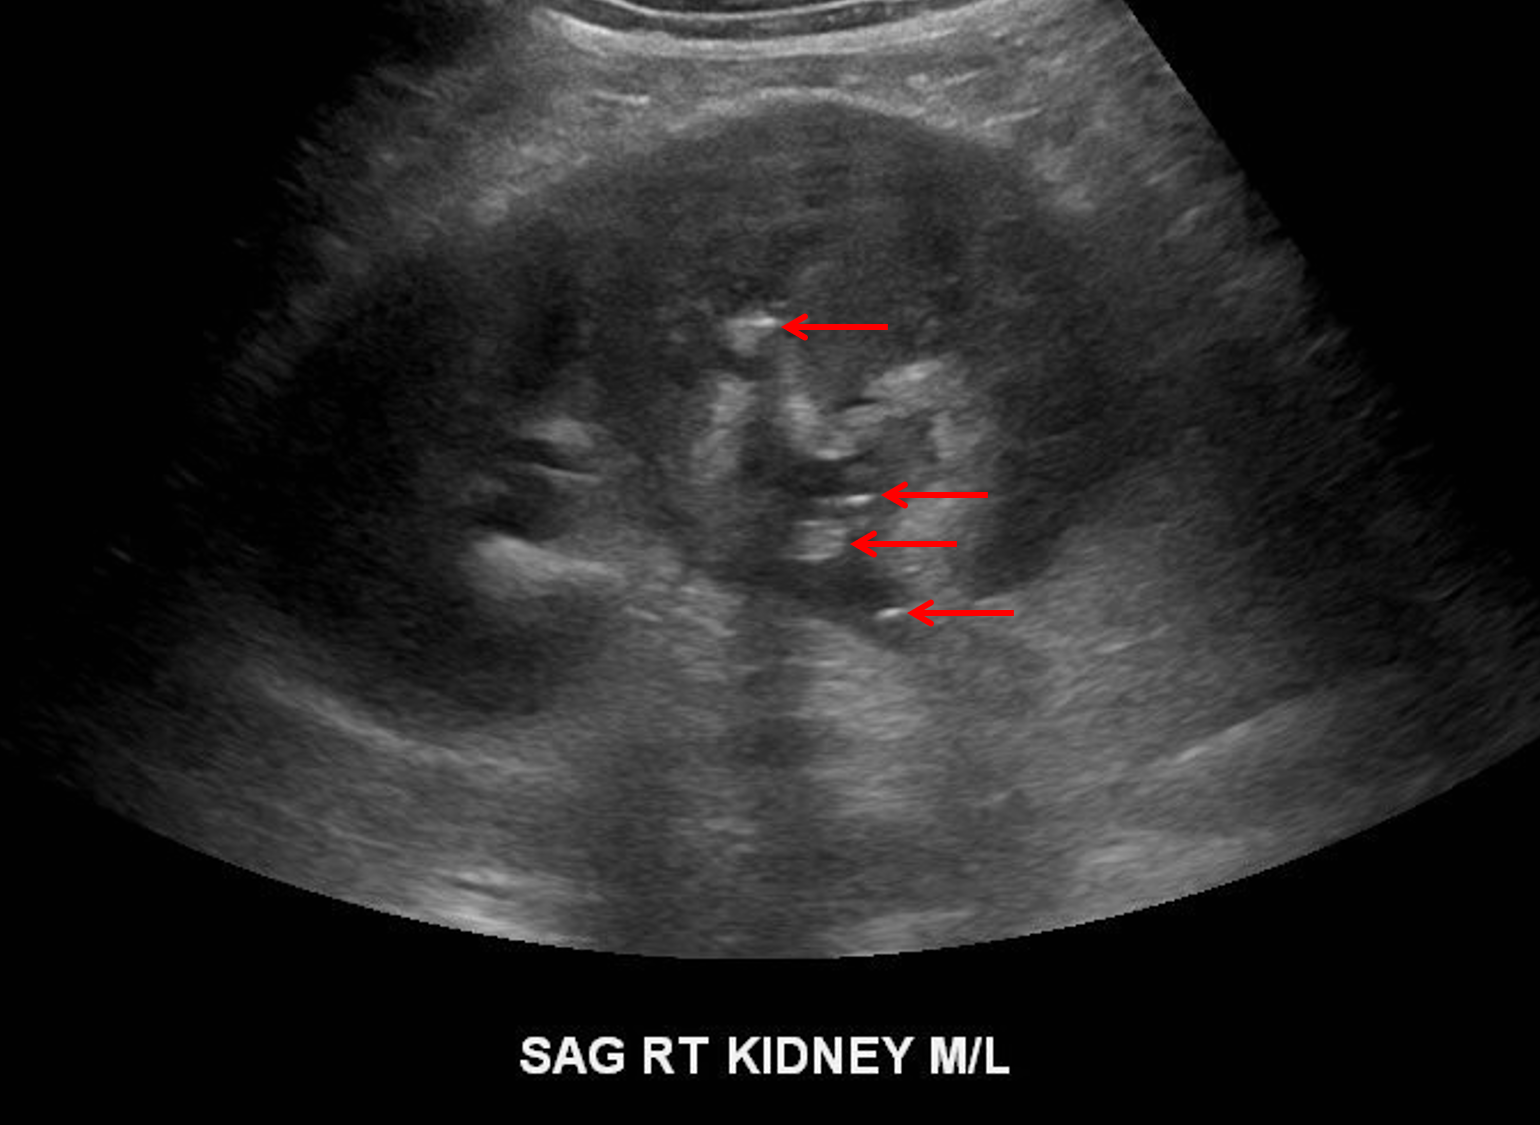

Ultrasound